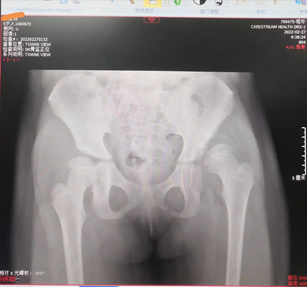

发育性髋关节脱位(DDH)是可能导致儿童残疾的重要疾病之一,也是对儿童骨科专家的重大挑战!幸运的是,目前在治疗此病,我还保持开放复位手术,从未发生再脱位。我无法确保以后手术,也一定不会发生再脱位,但是我一定会全力以赴、竭尽全力!手术效果展示:病例:黄佳X,女,2岁左DDH,行左侧髋关节开放复位(Pemberton)手术。术前X线片术后2月X线片术后1年X线片术后5年X线片

展示一下,这样的才是完美的髋关节脱位手术效果!(开放复位、Pemberton骨盆截骨、股骨短缩旋转截骨手术)迄今为止,我做过的最大年龄发育性髋关节脱位(9岁1月女孩,左侧发育性髋关节脱位)的全套截骨手术,手术效果完美,值得纪念!挽救了一个孩子,也就挽救了一个家庭,幸福感满满!那么普通公众该如何判断髋脱位手术效果的好坏呢?很简单,用正常侧的髋关节图像与患侧手术后的髋关节图像对比,如果看起来一样,手术一定做得很漂亮!